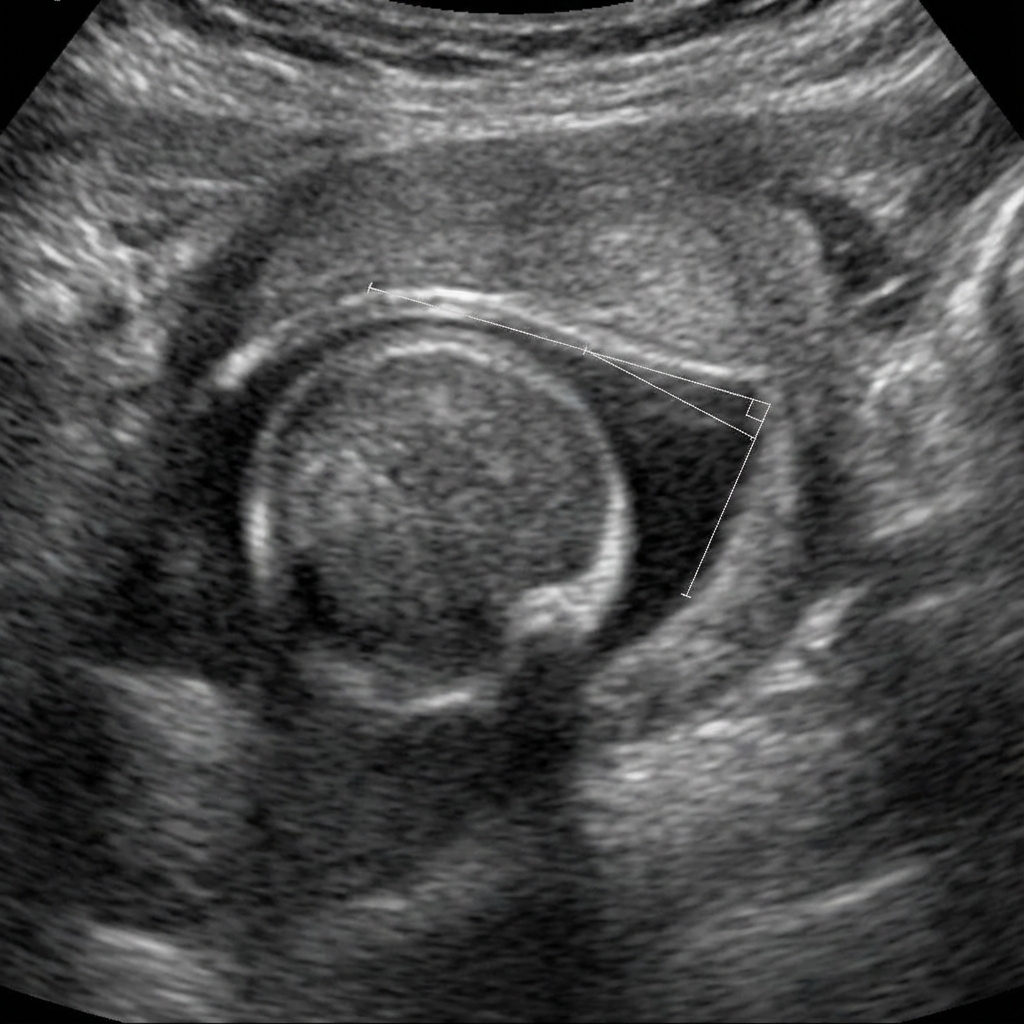

Coronal ultrasound image of infant hip demonstrating Graf Type IIc dysplasia. The alpha angle measures 48 degrees (normal >60 degrees) indicating deficient bony acetabular coverage. The beta angle is 65 degrees (normal <55 degrees) indicating increased cartilaginous coverage with displaced labrum. The femoral head is subluxed with poor containment. The iliac bone line, bony rim, and cartilaginous roof are annotated.

Interpret the ultrasound findings and explain the Graf classification system.